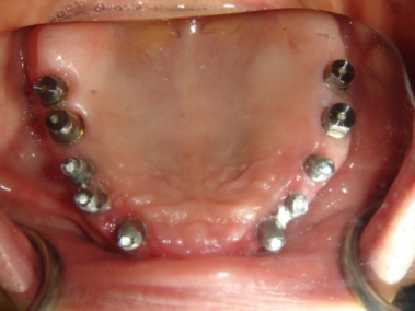

Doctor's note:

63 yr old female. Patient was referred to Dr. Kim’s office by another dentist as she presented with poor gum condition. She refused to wear dentures, and only wanted implants. Teeth were extracted, bone graft was placed into posterior maxilla via sinus augmentation, and implants were placed in after bone regeneration was complete.

Implant used:

Hiossen ET3

Treatment Duration:

14 months